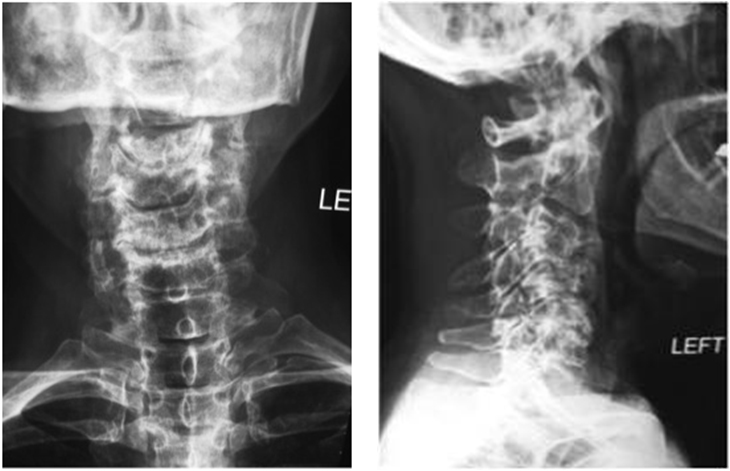

Από όλα τα παραπάνω αίτια της αυχεναλγίας συνηθέστερα είναι τα λεγόμενα “μηχανικά”.Στη συντριπτική πλειονότητα των περιπτώσεων η λήψη του ιστορικού και η κλινική εξέταση αποτελούν ακρογωνιαίους λίθους για τη διάγνωση του αίτιου της αυχεναλγίας. Σε σπάνιες περιπτώσεις που τα συμπτώματα χρονίζουν (διάρκεια μεγαλύτερη των 8 εβδομάδων) ο ασθενής πρέπει να υποβληθεί σε εκτεταμένο έλεγχο που περιλαμβάνει εξετάσεις αίματος και ειδικές απεικονιστικές εξετάσεις (ακτινογραφίες, αξονική ή μαγνητική τομογραφία Αυχενικής Μοίρας Σπονδυλικής Στήλης). Ο θεράπων γιατρός με βάση το ιστορικό του ασθενούς, την κλινική εξέταση και τον κατάλληλο, όταν χρειάζεται, απεικονιστικό έλεγχο θα θέσει τη διάγνωση του αιτίου της αυχεναλγίας και θα καθορίσει ανάλογα με αυτό τη θεραπευτική αντιμετώπιση.